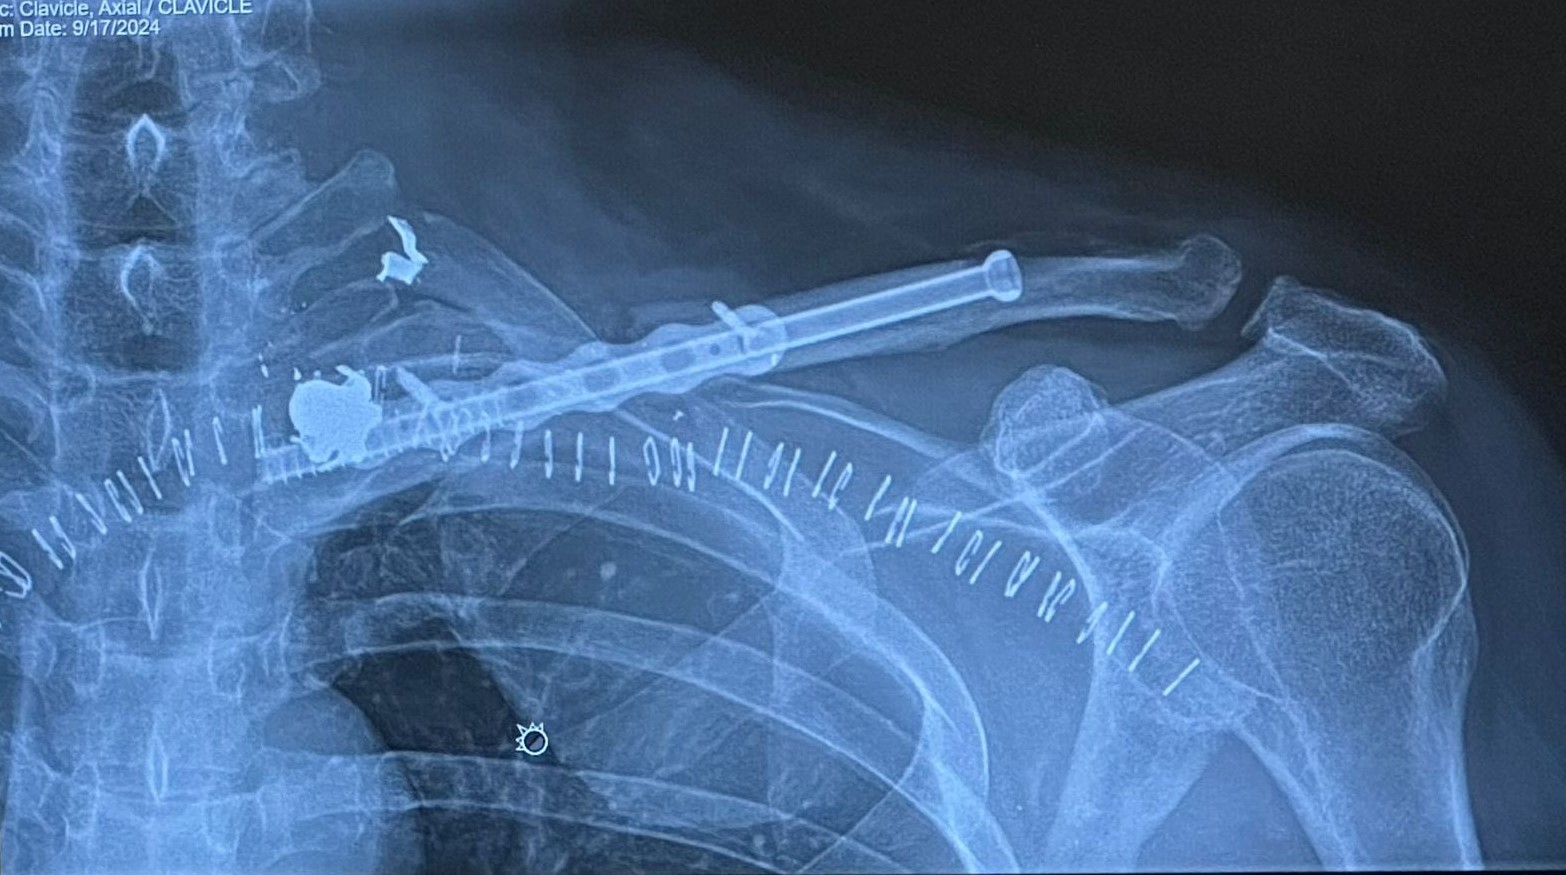

Milanés ya había compartido que le realizaron más de 30 transfusiones de sangre, pero ahora confirma que aún tiene cuatro fragmentos de bala en su cuerpo y un tubo de titanio en su clavícula izquierda, implementado para reemplazar la función de este hueso clave en la estabilidad del hombro.

El empresario, que también es activo en redes sociales, compartió imágenes que muestran un tornillo de al menos 10 centímetros en su clavícula. Este atraviesa su hombro izquierdo en dirección a la columna vertebral, revelando la magnitud de la intervención quirúrgica. Además, las imágenes evidencian unas 45 grapas metálicas que mantuvieron cerrada la herida, donde se extrajeron varios proyectiles.

Fuentes consultadas por la redacción de nuestro medio con conocimiento de tema, explicaron que el tornillo de titanio fue insertado para reemplazar de manera momentánea la función de la clavícula, un hueso crucial que mantiene el hombro elevado y estable, en conjunto con el omóplato y la articulación acromioclavicular. Esta estructura le permite mayor estabilidad en la articulación del hombro, algo esencial para su recuperación.